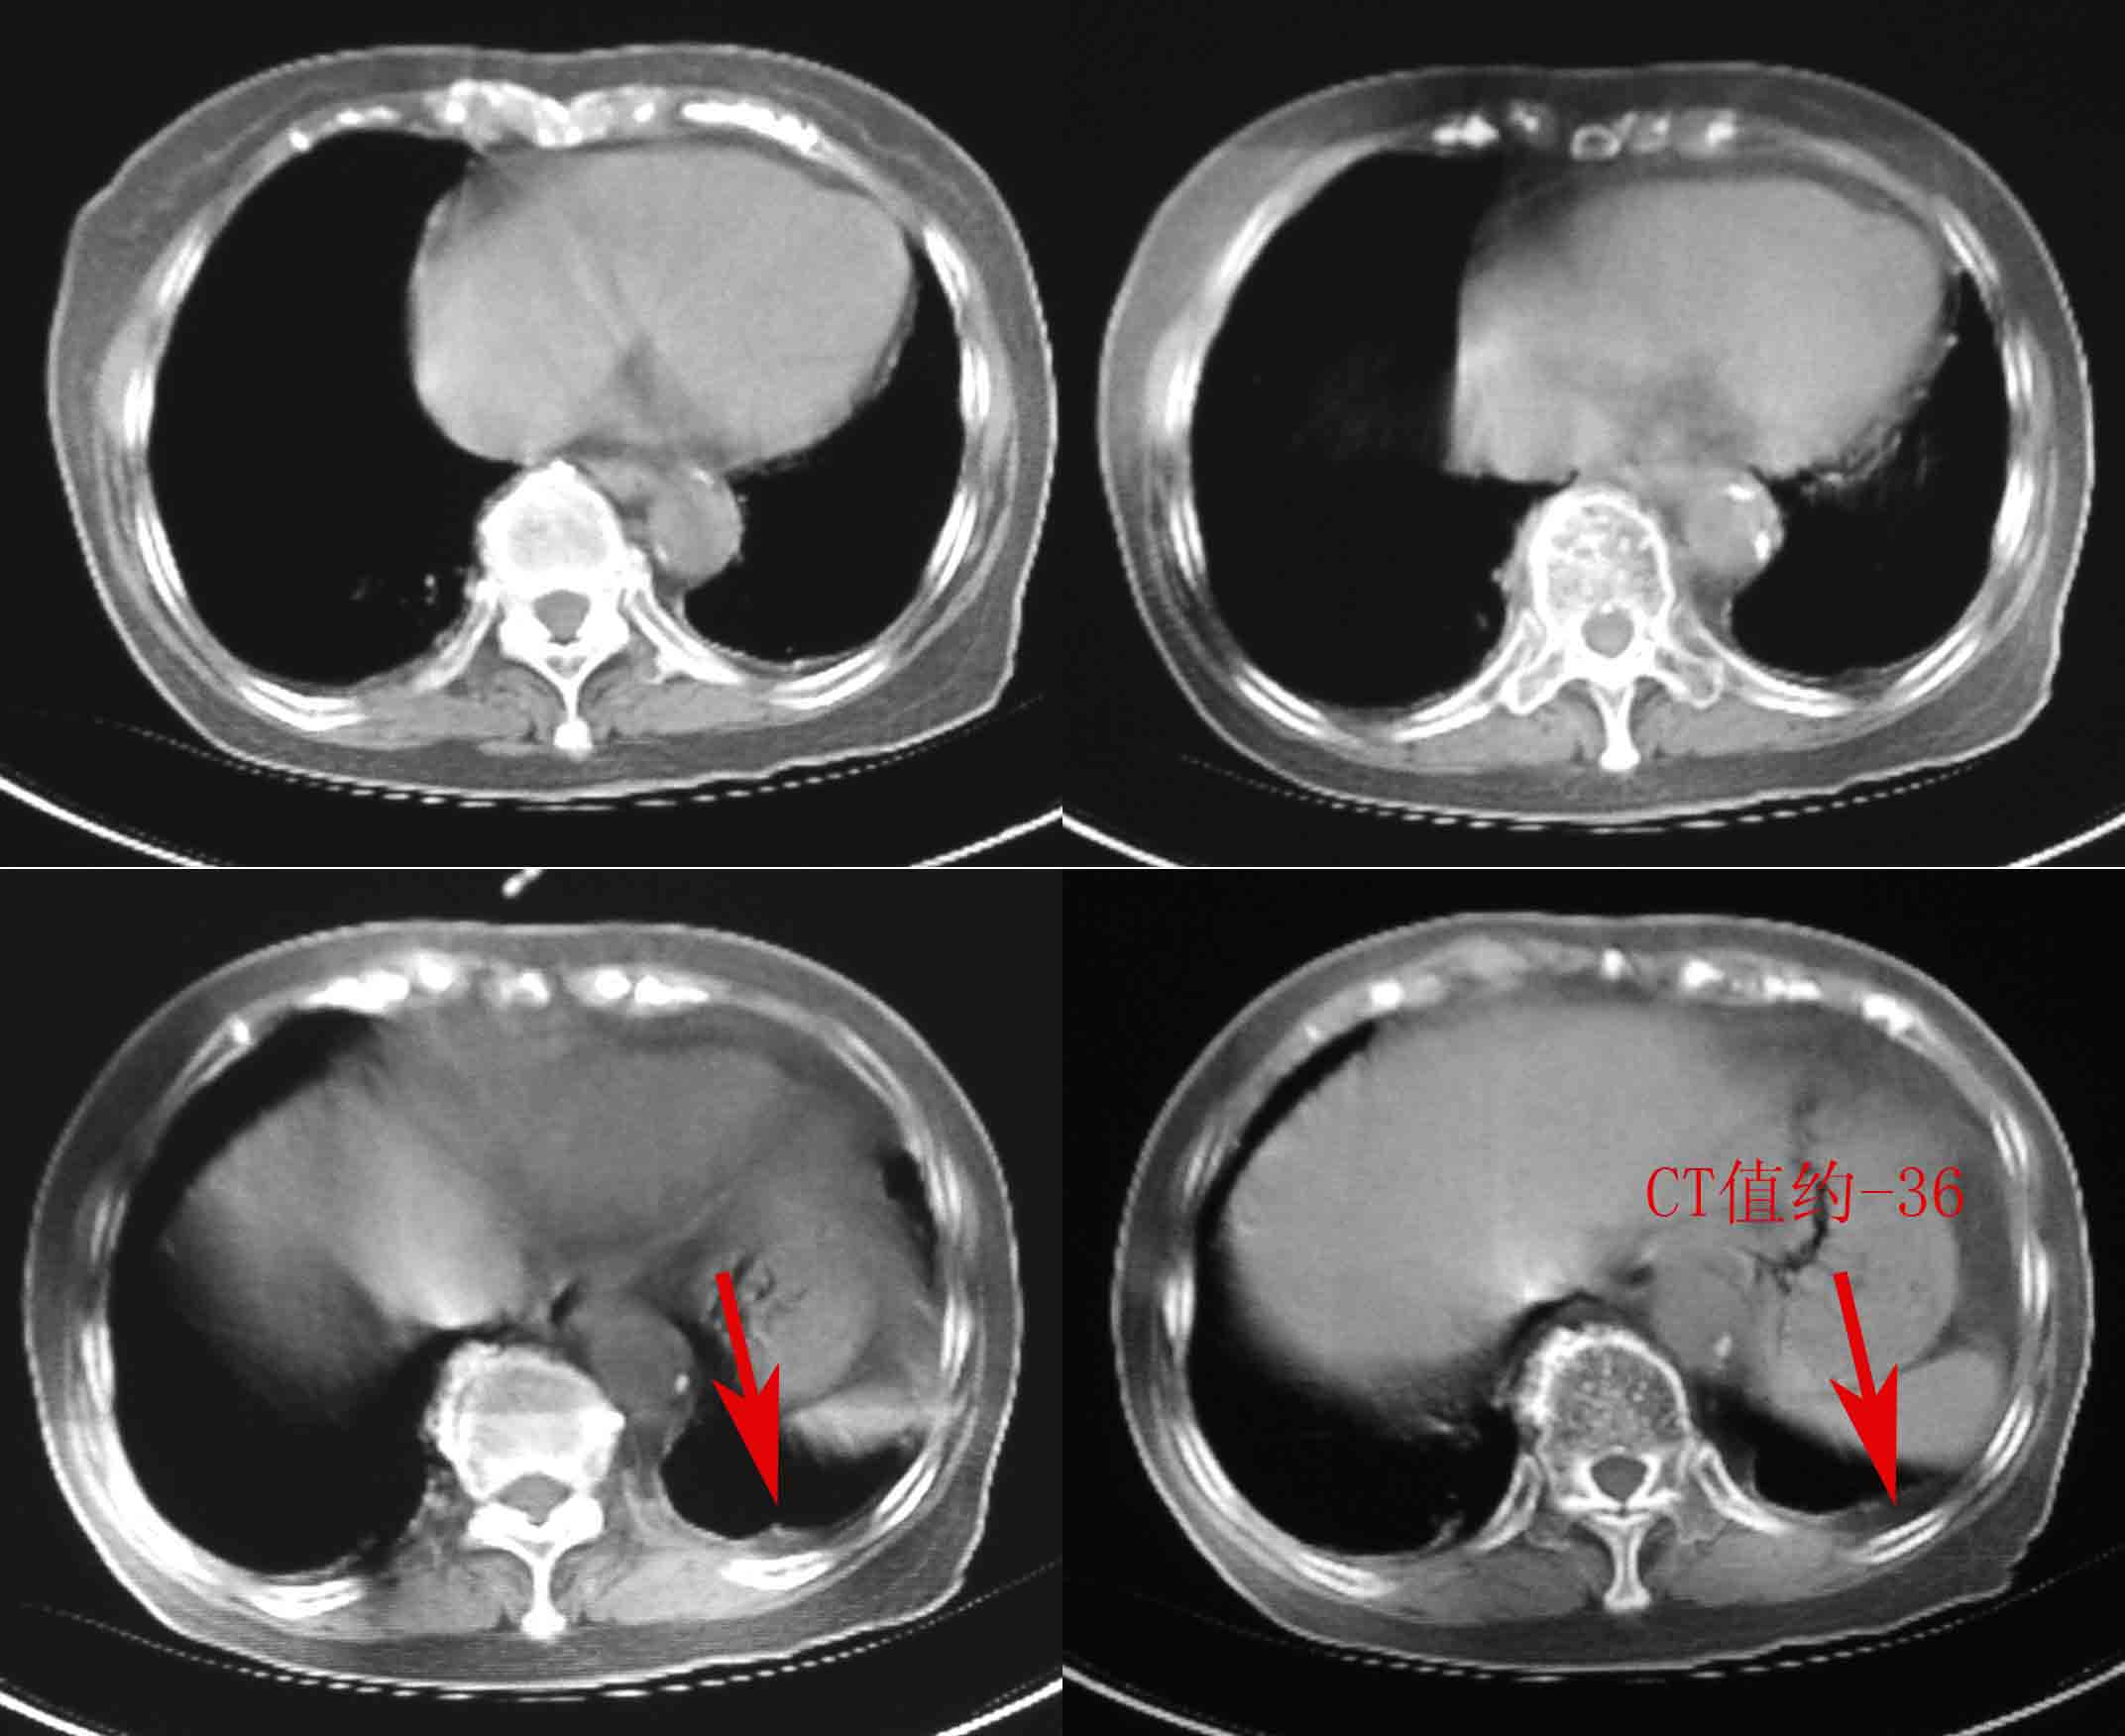

女69岁。时有咳漱、咳白色痰请老师们看看箭头所指是什么?ct值约-36.报告应该怎样写?谢谢!

考虑左后下胸内侧壁与胸膜之间脂肪影。

左后下胸内侧壁与胸膜之间脂肪影。

以下是引用随光逐影在2009-3-13 15:53:00的发言:[br]考虑左后下胸内侧壁与胸膜之间脂肪影。

考虑左后下胸内侧壁与胸膜之间脂肪影。支持

胸膜下脂肪影。